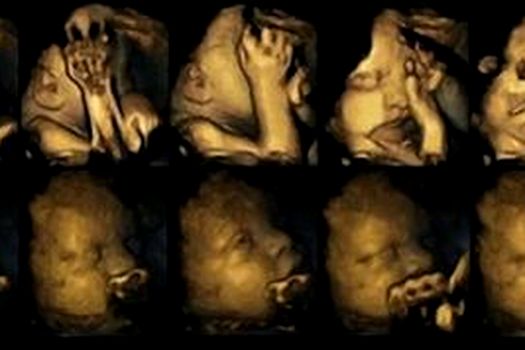

În imaginile de mai jos, fetusul cu o mama fumătoare se află pe rîndul de sus, iar fetusul cu o mamă nefumătoare este pe rândul de jos.

O echipă de cercetători din Marea Britanie, condusă de Nadja Reissland de la Universitatea Durham, a observat mii de mişcări subtile ale gurii şi atingeri ale feţei şi corpului, în cadrul a 80 de ecografii 4D realizate în cazul a 20 de fetuşi. Patru dintre ecografii aparţineau unor femei care fumau în medie 14 ţigări pe zi, iar celelalte 16 ecografii fuseseră realizate de gravide nefumătoare.

Toţi bebeluşii studiaţi s-au născut sănătoşi. Totuşi, fetuşii mamelor care fumau au prezentat un număr mai mare de mişcări ale gurii commparativ cu numărul în scădere al mişcărilor care sunt observate în mod normal în timpul dezvoltării intrauterine, spre finalul sarcinii. Cercetătorii au descoperit şi o întârziere în ce priveşte reducerea numărului de atingeri faciale în cazul fetuşilor ale căror mame fumau.